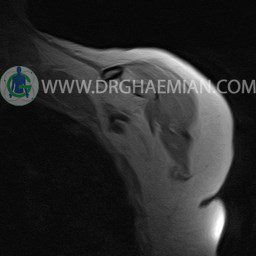

ام آر آی آتروفی عضلانی کتف بیمار

ام ار آی کتف یک روش تصویربرداری است که به وسیله آهنرباهای قدرتمند از قسمت کتف تصاویری ایجاد می کند. این نوع تصویربرداری از تشعشعات استفاده نمی کند. در این کیس آتروفی عضلانی کتف به همراه پارگی تاندون بالاخاری، بورسیت ساب دلتوئید و افیوژن مفصل دیده می شود.

LEFT SHOULDER MRI

(Without contrast)

Technique: Axial T1 and GE , coronal T1 , T2 , sagittal T1 , T2 .

REPORT:

The humeral head has normal configuration and articulates properly and parallelism with the normally developed glenoid .

The articular surfaces are smooth and show normal cortical thickness .

The bone marrow displays homogeneous , fat – equivalent signal intensity .

The glenoid labrum is intact on all sides .

The biceps tendon appears normal and occupies a normal position in the bicipital groove.

The other muscles that cover the shoulder joint appear normal , as do imaged portions of the lungs and soft tissues .

– Complete tearing of supraspinatus tendon with grade 2 retraction and muscle atrophy

– AC joint hypertrophy with subacromial – subdeltoid bursitis

– Glenohumeral joint effusion

are seen.